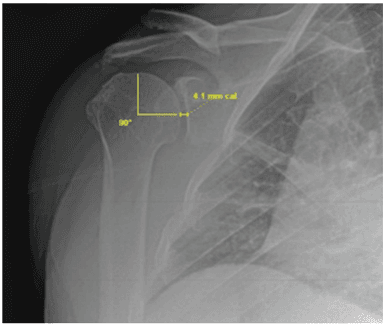

Outcomes after Micronized Fat Adipose Transfer for Glenohumeral Joint Arthritis and Rotator Cuff Pathology: a Case Series of 18 Shoulders

D.M. Robinson, C. Eng, M. Mitchkash, A.S. Tenforde, J. Borg-Stein, Muscles, Ligaments and Tendons Journal, 2020

Clinical use of autologous micro-fragmented fat progressively restores pain and function in shoulder osteoarthritis

Heather Vinet-Jones, Kevin F Darr, 2020